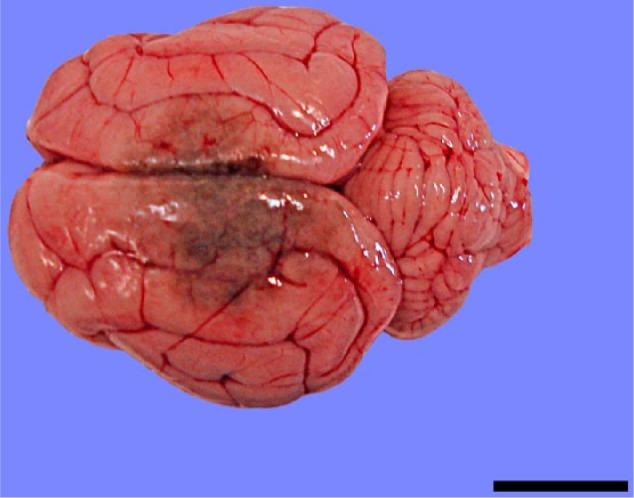

Cerebral pyogranulomatous encephalitis caused by in a 15-week-old domestic shorthair kitten.

A case of cerebral phaeohyphomycosis caused by is described in a 15-week-old domestic shorthair kitten.

Cerebral phaeohyphomycosis is a rare condition in cats caused by dematiaceous fungi. This report describes the clinical and histopathological findings in the youngest case documented in a feline, provides a brief review of aetiology, diagnosis, treatment and prognosis of cerebral phaeohyphomycosis and demonstrates the importance of molecular diagnostics in accurate mycotic species identification.